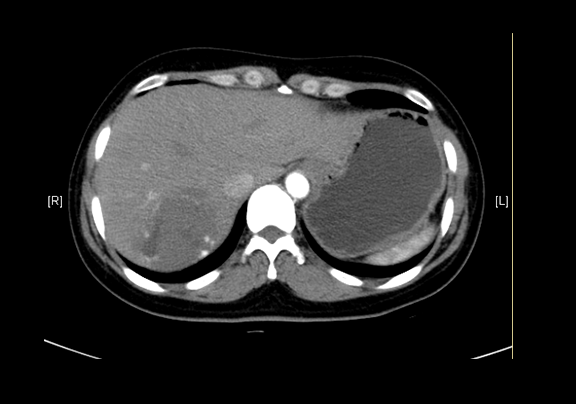

静脉期

平衡期

现病史:患者查体发现肝血管瘤半年,无腰背部放射痛、皮肤巩膜黄染、恶心、呕吐、寒战、高热、腹泻、血便、咳嗽、咳痰、胸闷、气短、尿频、尿急、尿痛、血尿,未予治疗。行上腹部增强CT示:肝血管瘤。

辅助检查: 下腹部增强CT示:肝内多发血管瘤可能性大,肝囊肿